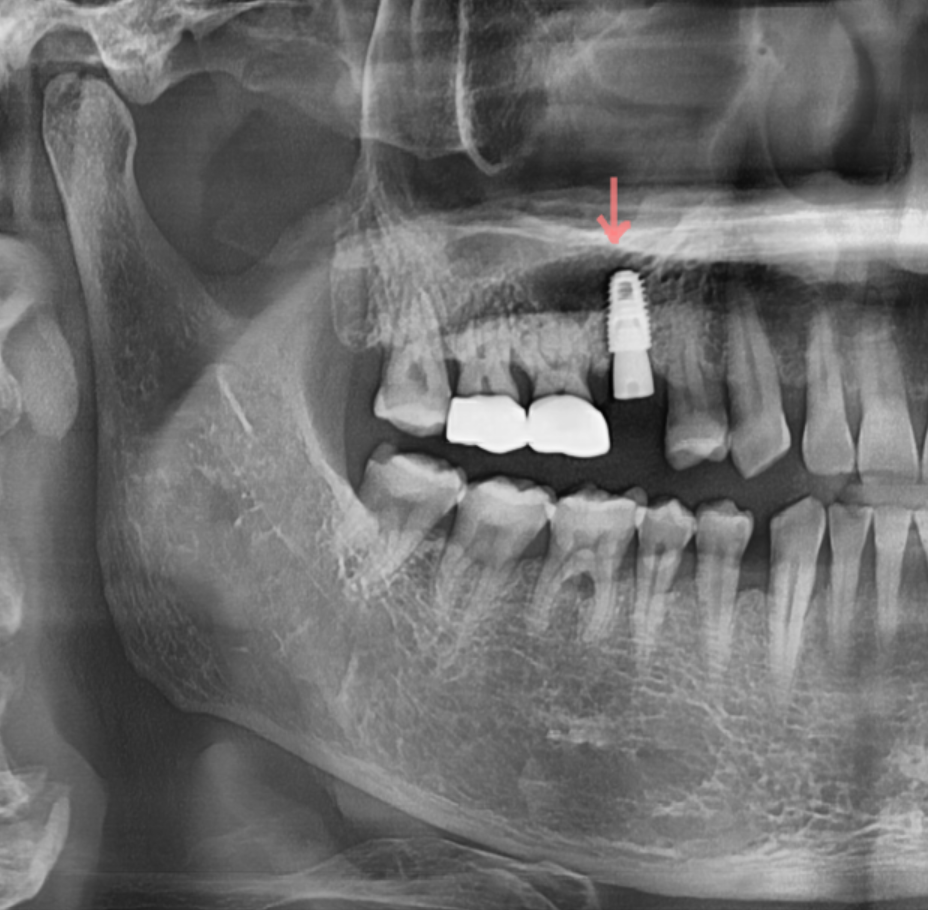

250313 1-2개 치아가 여러 치아 발치로 이어진 환자분

250325